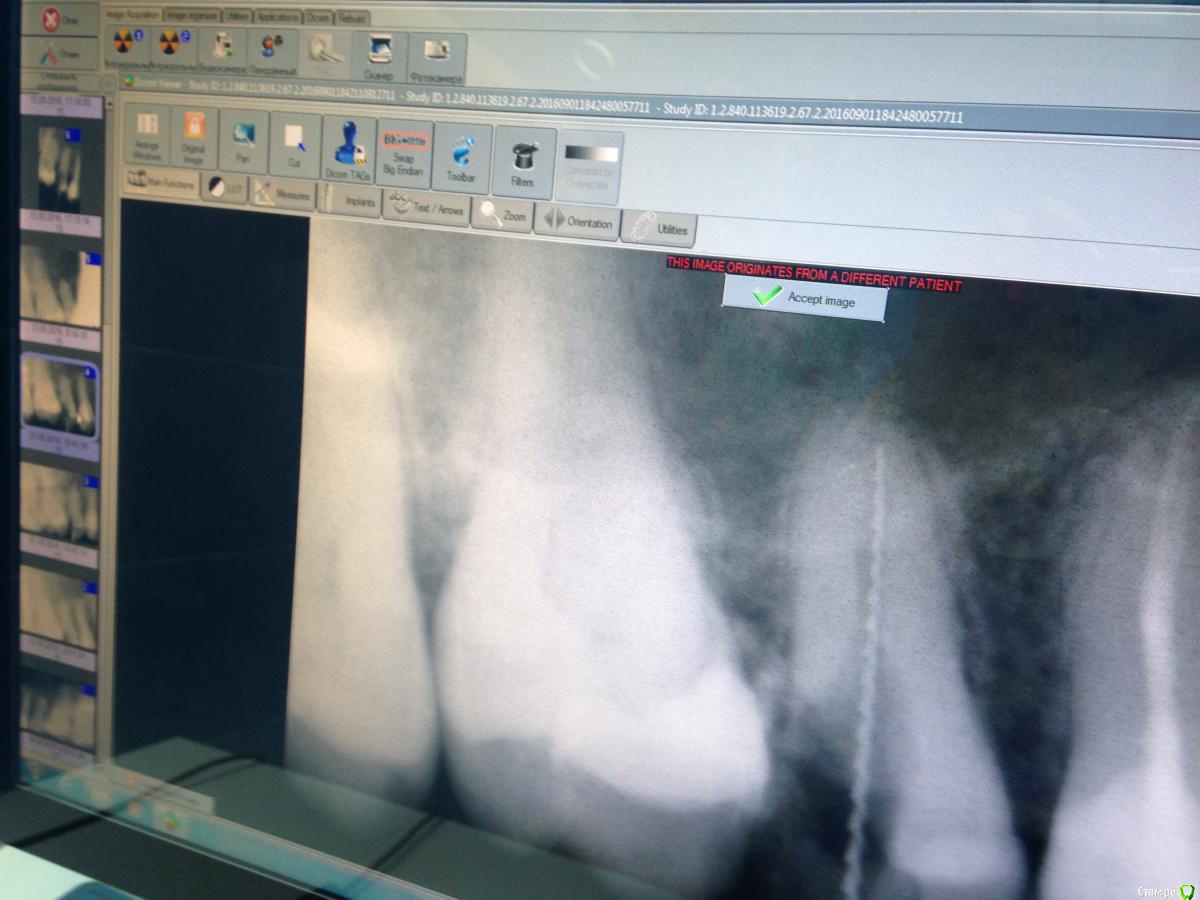

Malina11v Опубликовано 18 сентября, 2016 Поделиться Опубликовано 18 сентября, 2016 (изменено) Здравствуйте, хотела бы посоветоваться с коллегами. Такой случай: в начале июля приходила пациентка, ей другой доктор в нашей клинике поставила пломбы по глубокому кариесу на 15 и 16 зубы, через месяц она приходит еще к другой и говорит , что зуб болит уже месяц как, какой именно не знает, эта доктор принимает решение, что болит 15 и ставит депульпин. Через неделю пациентка приходит ко мне на обработку каналов, зуб Всю эту неделю ныл. В процессе обработки я расширяю канал до 40 и ставлю каласепт, Еще через неделю начинаю мыть парканом канал и пациенка указывает на резкую боль в области щеки и под глазом, понимаю что паркан зашел в пазуху, сразу начинаю мыть дистилированной водой обильно, ставлю крезофен и отправляю на неделю, так же пациенка указала на появление насморка, назначаю сосудосуживающие в нос и нимесил 5 дней, но гайморит у нее уже 10 лет как.Созваниваюсь с ней через пару дней , улучшения незначительные: зуб ноет, насморк есть, Назначаю сумамед 3 дня.через пару дней мою уже хлоргексином 2% и снова на каласепт. Через неделю: зуб эту неделю ныл, насморк немногл спал, но еще держится. Снова на каласепт и на две недели. Далее через две недели она приходит снова к другому врачу: зуб ноет , насморк есть, Приносит заключение ЛОРа с односторонним гайморитом , так же на снимках КТ определяется пломбировочный материал в пазухе и просвеь пазухи затемнен. Прилагаю снимки до лечения, во время обработки с инструментами и после пломбирования канала, На снимках с файлами в области верхушки видны белые тени, что это можеь быть? На кт их очень хорошо видно в виде полулунок, кроме каласепта и крезофена в каналах ничегл не было Изменено 18 сентября, 2016 пользователем Malina11v Ссылка на комментарий

Fibez Опубликовано 18 сентября, 2016 Поделиться Опубликовано 18 сентября, 2016 так может Вы нам КТ тогда и покажите? Раз их там хорошо видно? потому что тут кроме разбитой (резорбированной?) верхушки не видно ничего 1 Ссылка на комментарий

lightella Опубликовано 18 сентября, 2016 Поделиться Опубликовано 18 сентября, 2016 Каласепт - рентгеноконтрастный материал. Судя по тому, как разбит апекс, за верхушкой он и есть. 1 Ссылка на комментарий